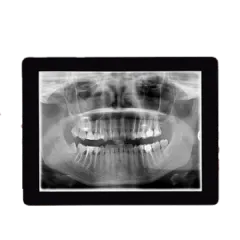

Digital Radiography

Digital radiography, an advanced form of X-ray imaging, captures detailed images of a patient’s oral structure using digital technology. This method allows for immediate image acquisition and eliminates the need for film, making the process faster and more efficient. One of the most significant advantages is the substantial reduction in radiation exposure — up to 80% less compared to traditional X-rays. This enhancement in safety is a critical factor in our commitment to providing care that not only achieves results but prioritizes patient health and well-being.

Furthermore, the quality of images produced by digital radiography is exceptionally high, enabling precise diagnosis and treatment planning. These images can be easily adjusted for contrast and brightness, allowing for better visualization of specific areas without the need for additional exposures. The ability to share these digital images electronically facilitates seamless collaboration with other dental professionals, ensuring comprehensive care.

By integrating digital radiography into our practice, North Coast Orthodontics leverages cutting-edge technology to improve every aspect of the orthodontic experience. From enhanced safety and comfort to superior diagnostic capabilities, our commitment to innovation is evident in the smiles we create.